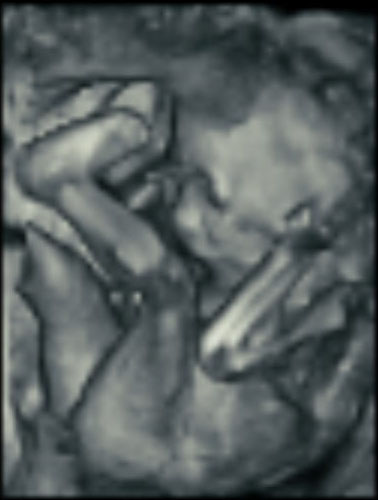

Here’s how ultrasound works in pregnancy: As early as 16 weeks, women can see a “fetal portrait” of their baby and determine its gender. Ultrasound technology has improved dramatically over the decades from flat, grainy black and white images to the current three-dimensional time experience.

Most hospitals offer some 3D scanning, but 3D ultrasound produces images that show the width, height and depth of a developing child. Rather than sending sound waves straight into the womb and recording when they bounce back as is common in 2D imaging, 3D ultrasound sends sound waves from different angles. A computer then renders a 3D image based on this data.

4D ultrasound adds movement as it occurs. The fourth dimension is time. You’re actually watching your baby live in 3D mode. How cool is that?